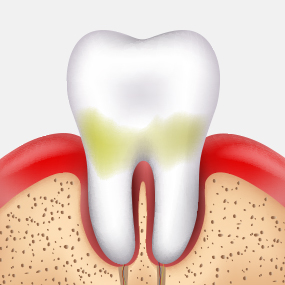

법랑질 충치

치아 겉면인

법랑질의 충치로 통증이 거의 없습니다.레진치료

상아질 충치

법랑질 안쪽에 있는 상아질까지 충치가 진행되어 뜨겁거나 차가운 음식을 먹으면 시린 증상이 나타납니다.

인레이

치수염 충치

상아질 안쪽 신경까지 염증이 진행되어 극심한 통증으로 참기 어려운

정도가 됩니다.신경치료 + 크라운

치주 괴사

치아 내부에 있는 조직이 괴사되고, 뿌리 주변의

염증으로 인하여 뼈가 점차 소실됩니다.발치 + 임플란트